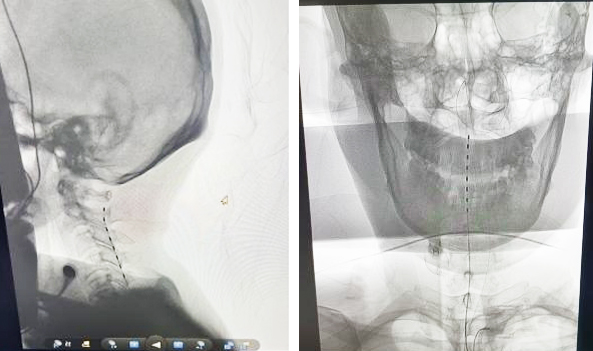

經(jīng)過(guò)充分術(shù)前準(zhǔn)備評(píng)估后,在介入室、手術(shù)室、麻醉科、器械科通力合作下,郝懷勇、葉翔、關(guān)家文醫(yī)生和介入室盧慶林主任,完成了我院第二例高頸髓脊髓電刺激促醒術(shù)。該患者開(kāi)機(jī)第三天在沒(méi)有拔除氣管切開(kāi)管的情況下,已經(jīng)能夠說(shuō)出自己名字,并能夠進(jìn)行短暫的語(yǔ)言交流,目前正在進(jìn)一步康復(fù)中。

該項(xiàng)技術(shù)適應(yīng)癥包括:重型顱腦外傷、腦缺氧、一氧化碳中毒、腦梗塞、腦出血等原因?qū)е碌幕杳曰颊摺T撌中g(shù)是一種微創(chuàng)手術(shù),并不損傷患者任何神經(jīng)組織,通過(guò)電刺激喚醒沉睡的腦細(xì)胞。團(tuán)隊(duì)會(huì)依據(jù)患者的個(gè)體化情況,充分術(shù)前評(píng)估,制定不同的治療方案,做到個(gè)性化治療,并設(shè)立了神經(jīng)外科昏迷促醒門(mén)診(每周五 郝懷勇),竭誠(chéng)為患者服務(wù)。